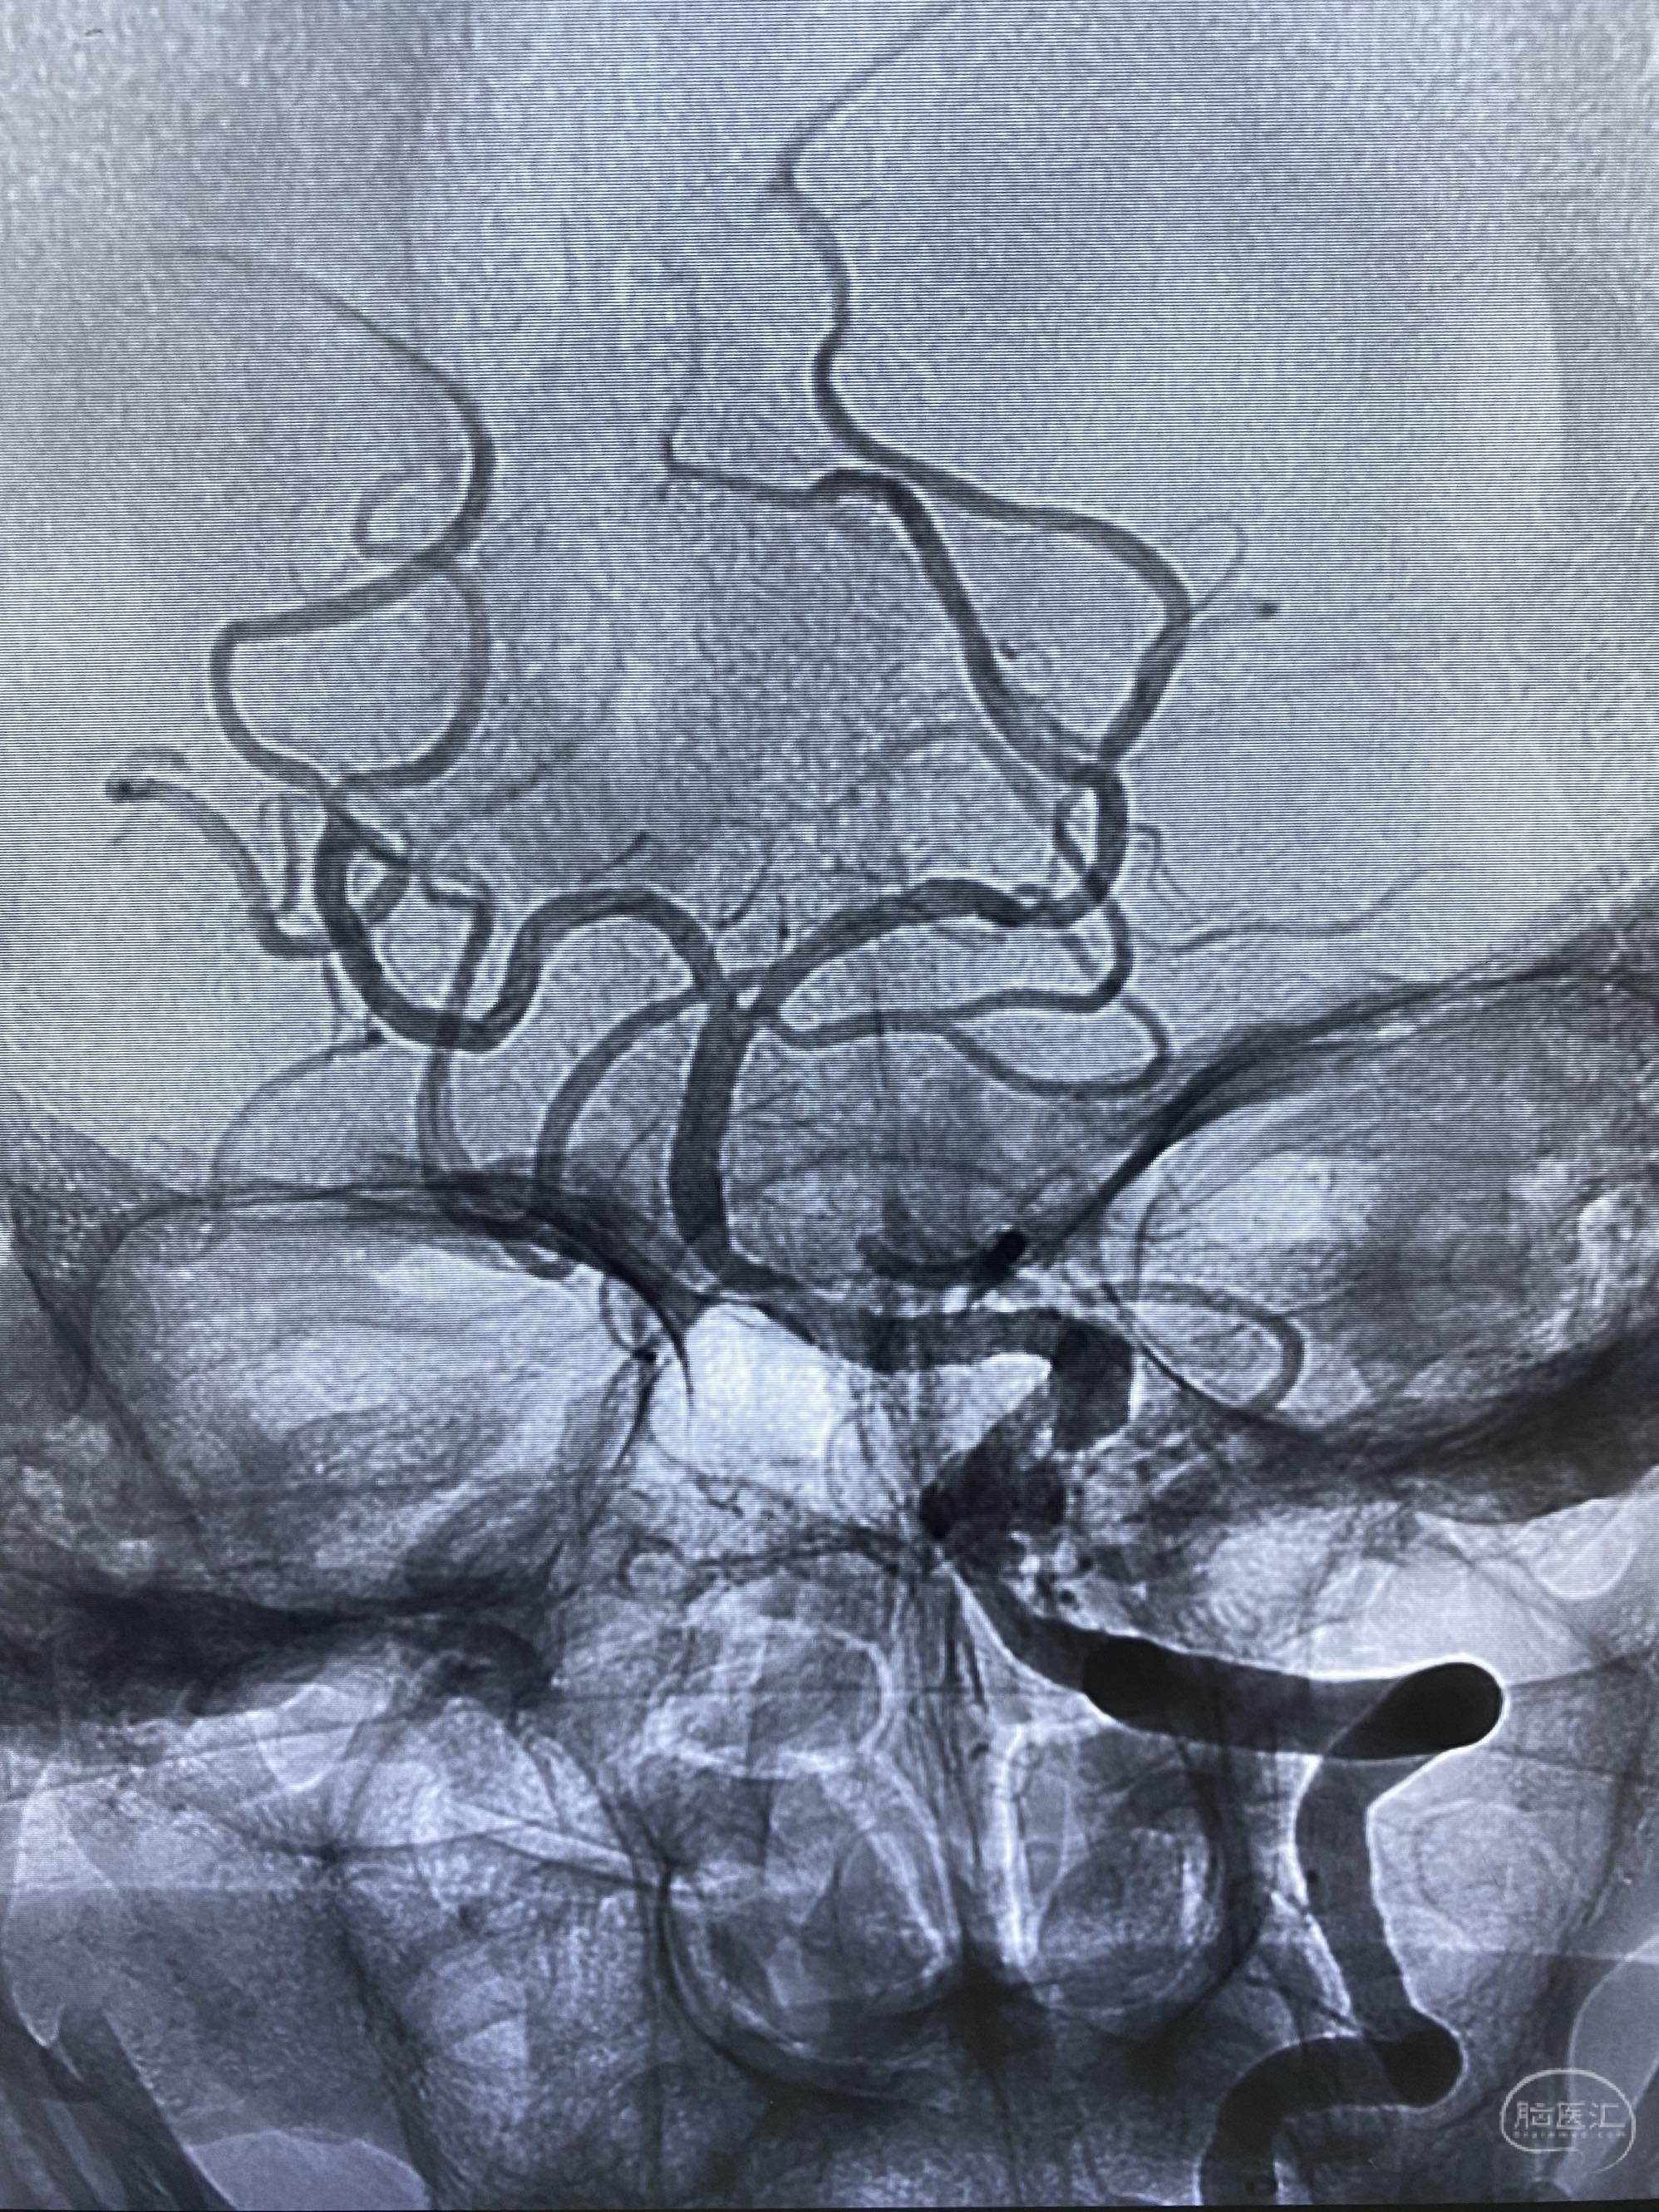

椎动脉颅内段多发夹层动脉瘤伴载瘤动脉狭窄pipeline flex植入

今日手术,TJG,M62Y,一期左侧颈动脉狭窄支架植入,二期椎动脉V4段多发夹层动脉瘤伴狭窄,常规支架辅助栓塞方法复杂又危险,血流导向装置植入快捷又安全。南阳市中心医院神经内科脑血管病介入团队pipeline flexFD植入两人导师资格。